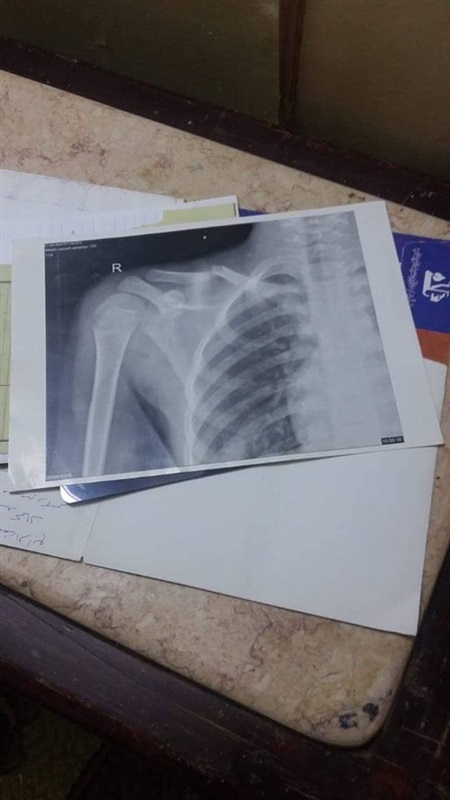

حيث أصيب "مازن" بكسر في عظمة الترقوة نتيجة إهمال مشرفة الأتوبيس المدرسي وتدافع الأطفال الامر الذى تسبب في سقوط مازن واصابته، ولم تكتف بهذا الأمر وقامت بالتعاون مع الأخصائي الإجتماعي بتقمص دور الطبيب ودهنوا مكان الكسر وعندما صرخ "مازن" قالوا له "انت بتسلبط"!

وروي والد مازن، أن المشرفة بتوصيله لباب المنزل وتركته دون تسليمه لنا أو ابلاغنا بما حدث معه، حتى شاهدته وذهبت به علي الفور الي المستشفي، وشخص الطبيب حالته بأنه مصاب بكسر في عظمة الترقوة يستلزم ارتدائه قميص خاص لحين التئام الكسر.